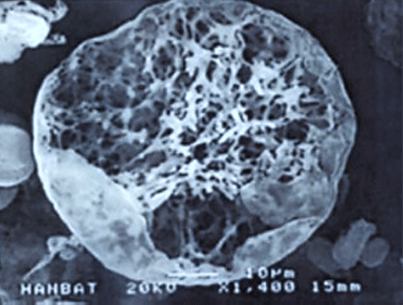

< 多孔性円形構造微細分子 >

쥬베룩의 입자 형태

大きさがとても小さくて丸いの

で結節ができにくく

生分解性で体外に排出されるので、

体内に残存物がほとんど残りません。

丸みを帯びた多孔性網状構造の粒子が

コラーゲンの再生効果を比較的長持ち